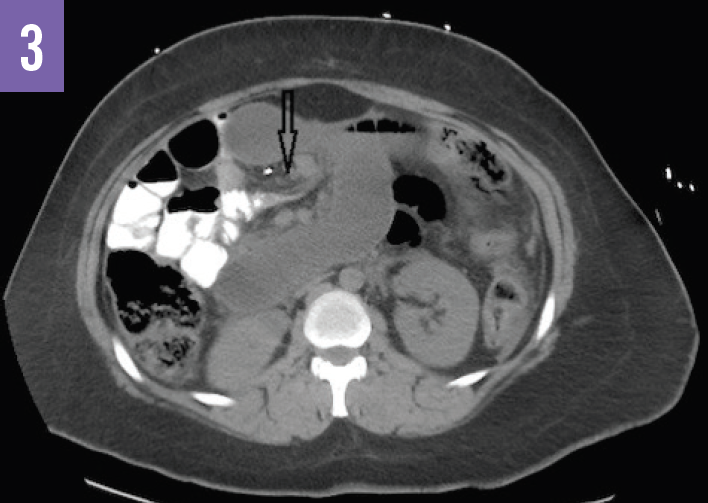

Diagnostic tests. An acute abdominal radiograph series was unremarkable for pneumoperitoneum but demonstrated a gastric air bubble (Figure 1). Computed tomography (CT) of the abdomen and pelvis with oral diatrizoate meglumine and diatrizoate sodium solution contrast medium demonstrated free air under the left hemidiaphragm and gastric pneumatosis (Figure 2), possible obstructions of the bilioenteric limb and within the common channel (Figures 3 and 4), and fat stranding at the pancreatic head (Figure 5).

Based on the imaging results, the patient received a diagnosis of internal hernia with perforation of the gastric remnant.